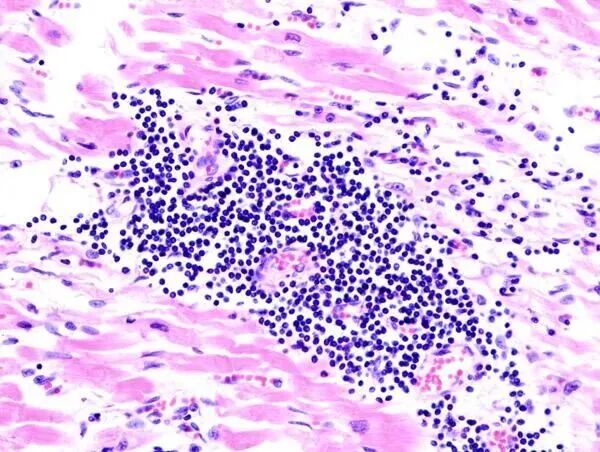

显微镜下,可以清晰的看到心肌组织会呈现局限性或弥漫性的急性或慢性炎症性病变,有炎性细胞浸润、心肌细胞损伤坏死及纤维化等病理改变。

图片

△ 病毒感染后的心肌细胞显微镜照片